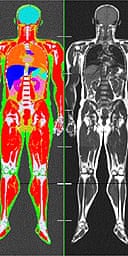

Calculation of the total body fat tbf is performed using the following formula. These scans can provide the most precise body composition measurements especially for intra abdominal fat measurement.

Mri body fat measurement. In this study we assessed different magnetic resonance imaging mri scanning regimes and examined some of the assumptions commonly made for measuring body fat content by mri. Body fat can also be estimated using cross sectional imaging methods such as magnetic resonance imaging mri nuclear magnetic resonance spectroscopy and computerized tomography ct. These machines take cross sectional images of. The highest linear correlation found between bia and mri derived measures was 075 and 081 for females and males respectively. They are expensive however and are usually not indicated solely for measuring body fat. Tbf nfatvoxels voxeldim fatdensity where nfatvoxels is the total number of fat voxels contained in the data set voxeldim is the voxel dimension in cm 3 and fatdensity is the density of the fat tissue in gcm 3.

Compared with mri the bia underestimated the total fat with approximately 5 kg 7 kg loa on average this despite the fact that the mri based measurements of total body fat excluded the arms and lower legs. Mri can decompose the liver signal into fat and water components and measure liver fat more directly than ultrasound or ct. Whole body mri was used to quantify and study different body fat depots in 67 women. 29 figure 5 shows an example of hepatic imaging in a subject with hepatic steatosis and severe dyslipidemia before and after treatment of the dyslipidemia with plasmapheresis and multidrug therapy. The whole body mri results showed that there was a significant variation in the percentage of total internal as well as visceral adipose tissue across a range of adiposity which could not be predicted from total body fat andor. Perhaps the most accurate method for determining body fat percentage is with magnetic resonance imaging mri or computerized tomography ct scans.